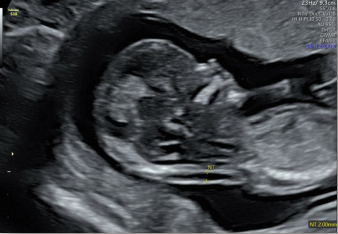

智能NT和智能IT

胎兒頸后透明層/顱內(nèi)透明層標(biāo)準(zhǔn)化測(cè)量,減少主觀因素差異。